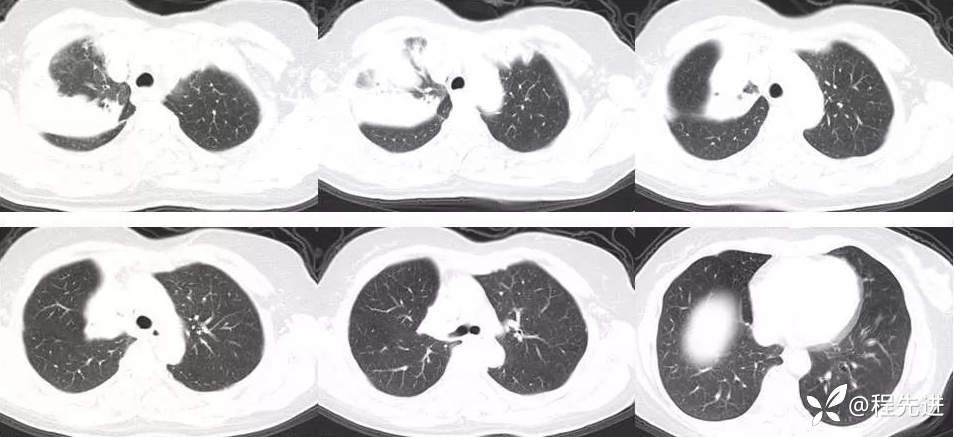

外院胸部CT平扫:右上肺病变,其内见散在高密度影